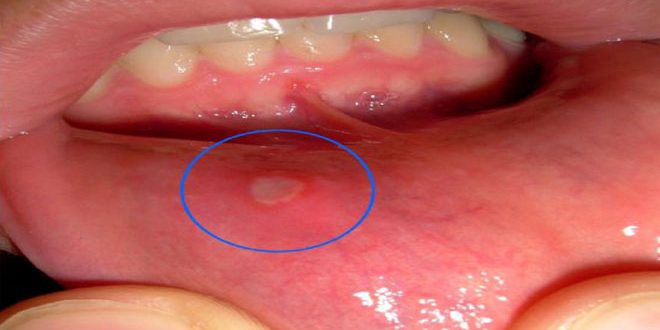

والقلاع كما يوضح اختصاصي الأمراض الجلدية الدكتور حميد سليمان من أمراض المناعة الذاتية يبدأ ظهوره على الأغشية المخاطية في الفم والبلعوم والحنجرة كفقاعات تنفجر وتحل مكانها تقرحات ويحتاج شفاؤها فترة تتراوح بين أسبوع وأسبوعين .

ويوصى سليمان بمراجعة الطبيب عند حدوث هذه الاندفاعات الفموية بشكل مبكر تفادياً لحدوث أي اختلاطات مشيراً إلى إجراءات تساعد في تخفيف الألم وتسريع الشفاء والتئام التقرحات كاستخدام فرشاة أسنان ناعمة وتجنب الأطعمة الحمضية والساخنة والقاسية وعدم استعمال معاجين أسنان تحتوي سلفات الصوديوم وتناول مكملات غذائية مثل فيتامينات ك وب 6 و12 والزنك .

وبينما لايزال سبب تقرحات الفم غير معروف على وجه التحديد أشار طبيب الجلدية إلى عوامل تزيد احتمالية ظهورها كإصابات البطانة الفموية التي تنتج عن عض باطن الخد أو الحشوات السنية غير المناسبة والخدوش الناتجة عن فرشاة الأسنان والتبدلات الهرمونية لدى السيدات .

وأضاف سليمان أن الحساسية تجاه بعض الأطعمة والتوتر والقلق وقلة النوم ونقص الحديد وفيتامين ب12 قد تسبب ظهور هذه التقرحات.